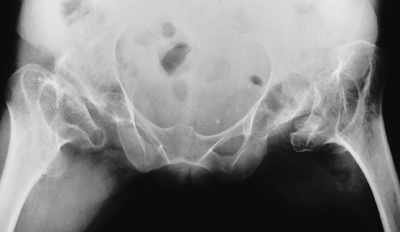

proximal femoral epiphyses progressively deform, and even subluxate in

some patients. Epiphyseal flattening and hinge abduction develop in

many patients (96). Arthritic changes develop

by early to middle adulthood. The knees usually have flexion

contractures that result from a combination

of ligamentous contracture and epiphyseal deformation (Fig. 8.17).

Excessive valgus is also common. As many as one fourth of these

patients have a dislocated patella. Degenerative joint disease of the

hips and knees develops in early to mid-adulthood.

![]() |

|

Figure 8.17

The extremities as well as the feet are involved in diastrophic dysplasia. Joint contracture is accompanied by epiphyseal deformity, as this knee radiograph illustrates (A). A rigid, severe equinovarus foot is common (B). |